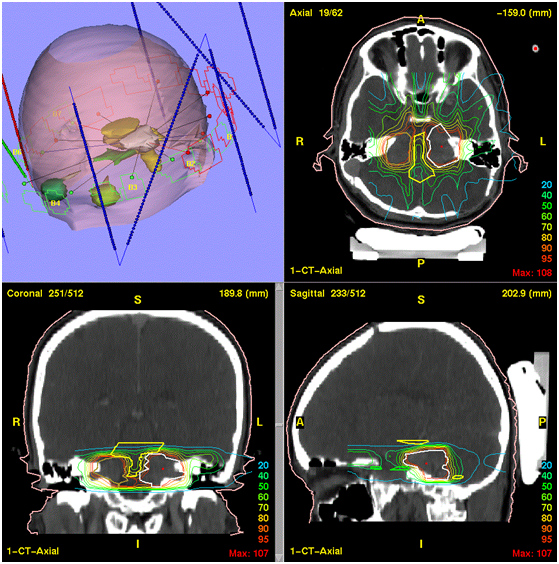

Intensity-modulated radiation therapy (IMRT)

This kind of radiotherapy is a three-dimensional new method that uses X-rays of varying intensity at the same time for irradiation. This method has a Multileaf Collimator, which enables the beams to accurately radiate and formulate the beam accurately. This method is less harmful than other methods. The radiation tube rotates around the patient and the tumor is irradiated from different angles (Figure 3). The IMRT method is more complex and longer than 3DCRT. In this way, healthy cells are less irradiated than cancer cells. This method is most commonly used for brain, head and neck, and liver tumors, and is not applicable to all cancers (Figure 4). This method has been used less frequently in oncology centers, because it is highly specialized.20–23

Figure 4 Simulation of treatment by method IMRT. 23